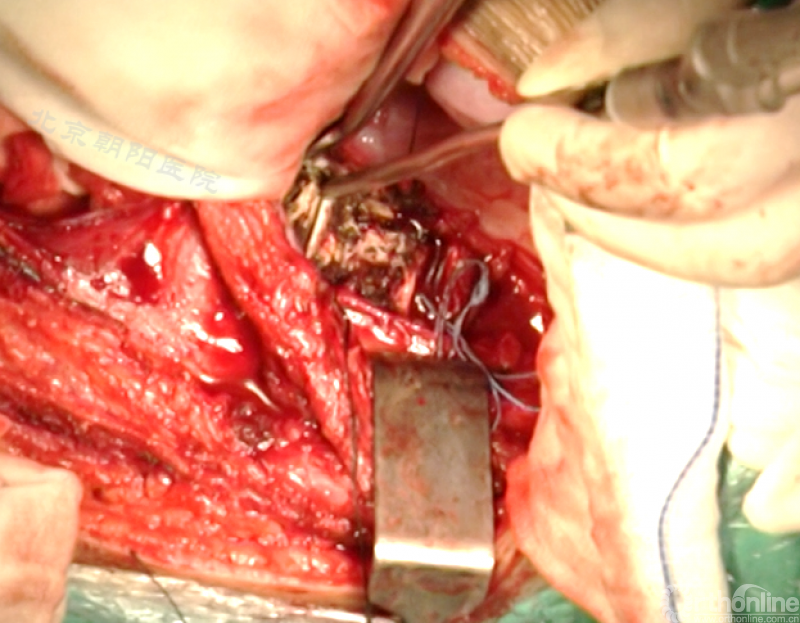

切开纤维环,去除终板椎间盘组织,直至纤维环的后侧边缘,对于严重侧凸如果需要可至后纵韧带。

进一步使用刮匙和髓核钳完整去除椎间盘组织和终板,营造植骨面。

胸腔侧、腹腔侧螺钉全部置入后,骨移植物植人的越靠近后纵韧带或者纤维环的后缘越好。